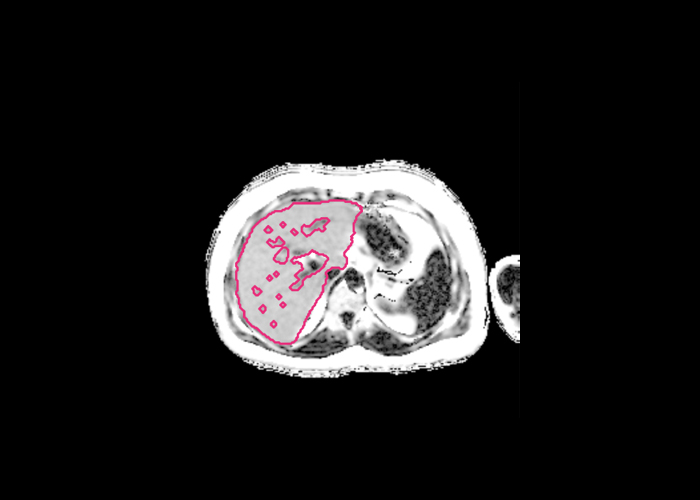

A través de secuencias de mapeo de T1, medimos y cuantificamos la fibro-inflamación hepática.